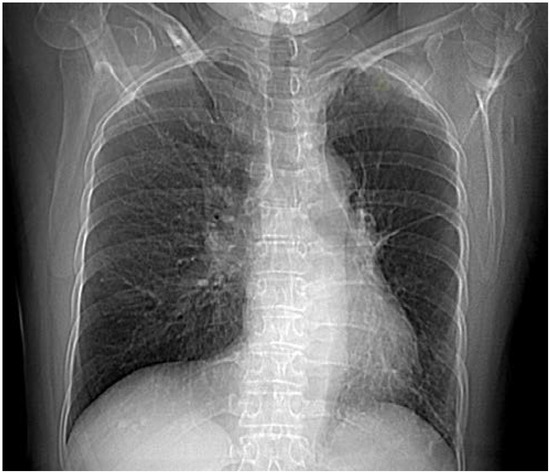

Introduction: Pasteurella multocida colonizes the oropharynx of various domestic and wild animals. In humans, respiratory tract P. multocida infection is the second most frequent localization and usually manifests as pneumonia. Unilateral absence of pulmonary artery (UAPA) is a very rare congenital anomaly. Adult patients with UAPA are usually asymptomatic or their symptoms are nonspecific. Case report: We report a female patient with hemoptysis admitted to our clinic where we isolated P. multocida in sputum. The organism was also isolated from nasopharyngeal swab of her dog. During hospitalization, she was also diagnosed with UAPA and chronic obstructive pulmonary disease (COPD). Discussion: Respiratory P. multocida infection develops more commonly through contact with animal secretions. It occurs most often in immunocompromised patients and in individuals with comorbidities. Hemoptysis very rarely follows P. multocida infection while it is common in cases of UAPA due to existing developed collateral circulation especially in older patients. Conclusions: Ceased hemoptysis after adequate treatment and no recurrence of it over six years of following up the patient led us to conclude that the cause of hemoptysis was P. multocida infection and not UAPA which was more likely to be the case. Full article

Figure 1